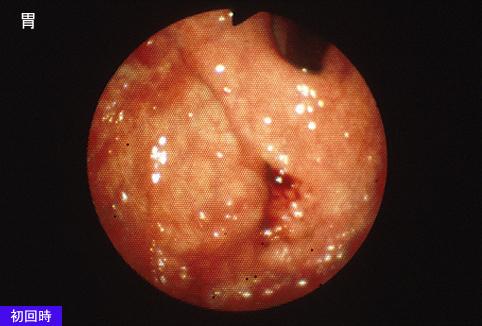

Cáncer Avanzado de Estómago tipo 4, que se diagnosticaban múltiples metástasis al esófago

Tumor Epitelial Maligno/Adenocarcinoma

estómago(región)/mas de dos

Endoscopia

Tipo 4(Tipo difusamente infiltrado)/

40 -